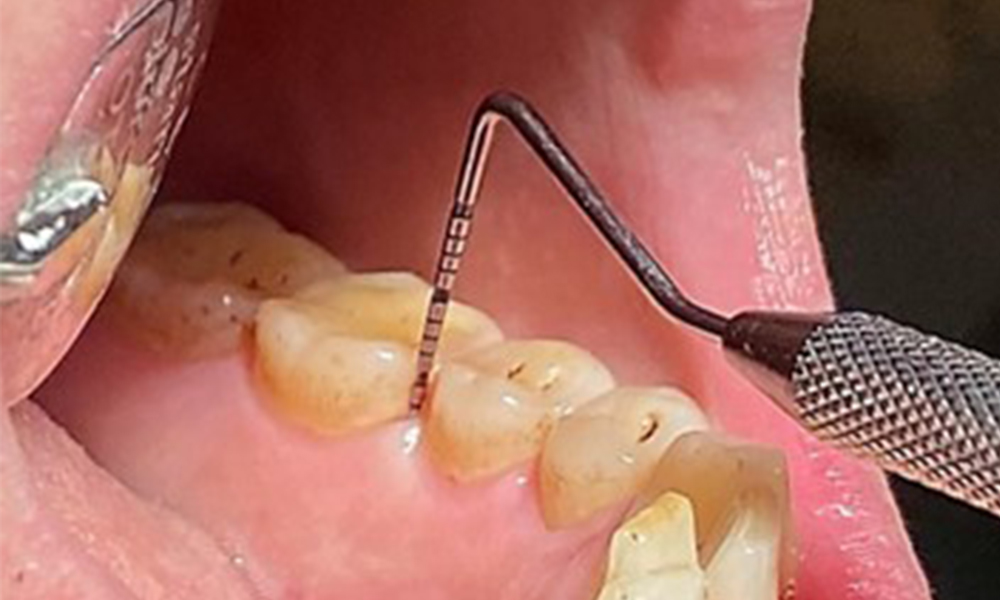

Due to the otherwise favourable general medical condition, the needs determined during the intraoral examination will be decisive for their treatment. It will be essential to periodically determine the probing depths. Gingival bleeding decreases in smokers, which is why the clinical diagnosis of periodontitis can only be made by probing (Fig. 7). Placing exclusive focus on the determination of bleeding indices may obscure existing periodontitis or gingivitis. (5)

The periodontal status should be thoroughly examined once a year. The detection of plaque using a staining agent may be a source of motivation. The assessment of intraoral findings, buccal surfaces and lingual mucosa are particularly important in smokers, as they will facilitate the detection of any pathological changes at an early stage (6). Photographic documentation allows the assessment of the development of potential pathological mucosal lesions over time. Referral to a specialist may be required to obtain and test tissue samples. Imaging procedures also support the motivational discussions with the patient. They may allow improvements to be highlighted over the course of subsequent preventive dental appointments.